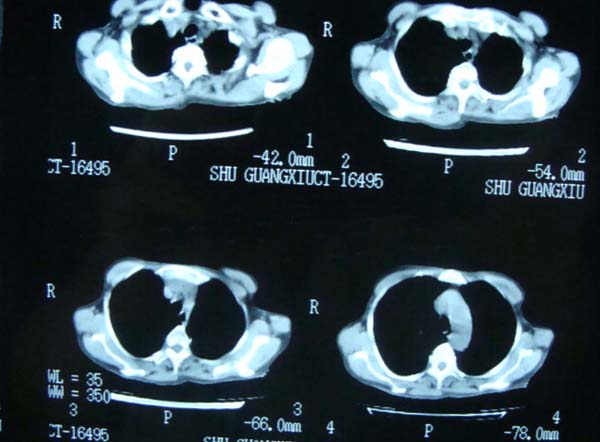

标题: CT13799:风心?肺动脉发育异常?

xxx女.72岁,胸闷不适,一侧下肢水肿.肺窗没见异常.不上传.

肺动脉根部,右室增宽;肺门小;是什麽征象///

右肺动肺截断.肺动肺脉高压

主肺动脉扩张,腹水.

考虑:1、肺动脉高压(原因?);

2、肝硬化伴腹水。